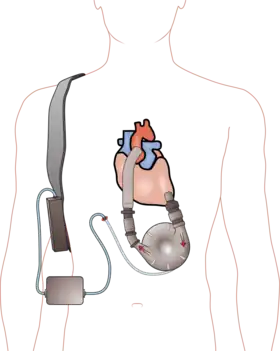

| 142 | 1990 | Pierce-Donachy Ventricular Assist Device

The world's first implantable heart pump to receive widespread clinical use. |

|

1973 | Hershey | Pennsylvania | United States | ASME brochure |